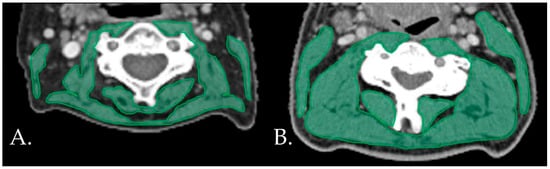

The inter-rater reliability of the main observer was excellent for both the CT (ICC = 0.994, 95% CI 0.982–0.998, p < 0.001) and the MRI (ICC = 0.985, 95% CI 0.970–0.993, p < 0.001). The mean (SD) SMIs were 42.40 ± 6.75, 44.95 ± 6.01, and 26.87 ± 6.01 cm2/m2 for the total population, male patients, and female patients, respectively. Seventeen (29.8%) patients were diagnosed has having low SMIs. Figure 1 shows examples of patients with and without low SMIs. Frequencies, means, and medians for the clinical characteristics, frailty domains, and postoperative outcomes for the total population and for the patients with and without low SMIs are displayed in Table 1, Table 2 and Table 3, respectively.

Figure 1.

Examples of patients with (A) and without (B) low SMIs on the neck CT.s CT: computed tomography. SMI: skeletal muscle index.